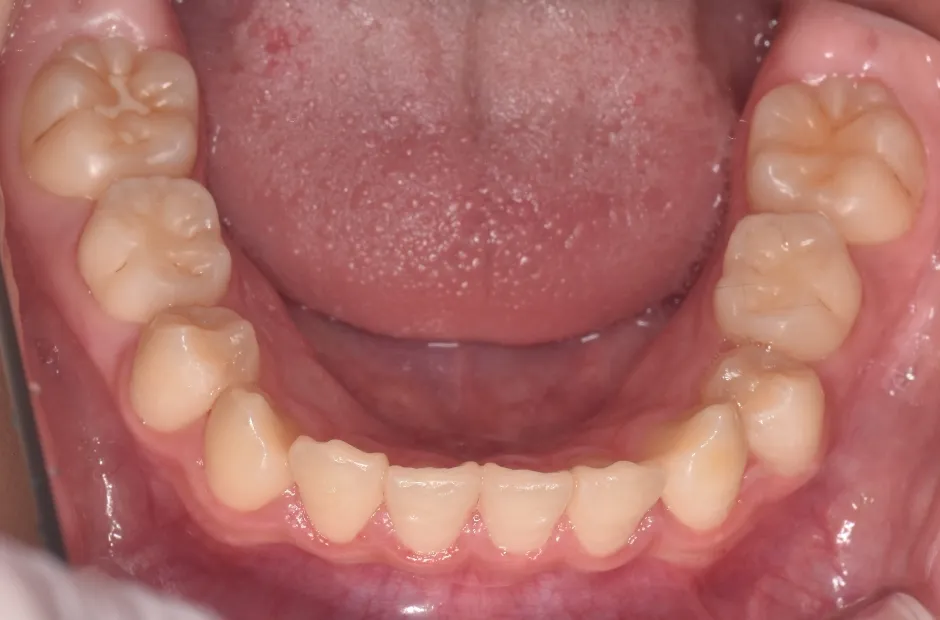

拡大床装置

叢生

| 診断名・主訴 | 叢生 |

|---|---|

| 年齢・性別 | 10歳・女性 |

| 治療期間・回数 | 2年半 |

| 治療に用いた主な装置 | 拡大床装置 |

| 抜歯部位 | なし |

| 治療費 | 30万円(税抜) |

| リスク・副作用 | 装置による違和感・疼痛・歯肉退縮・歯根吸収・虫歯のリスクなど |

治療前

治療中

治療後